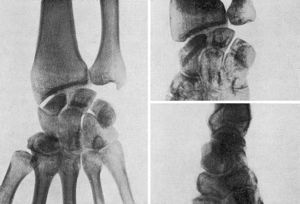

La extirpación de todo el escafoides o de un fragmento del mismo (Dwyer y Cave, Gurd, Hirsch, Dewey, Sashin, etc.) no ha dado buenos resultados provocando una grave alteración de la función de la muñeca (Vernon Luck, Kemper) (Fig. 1). Las perforaciones múltiples a lo Beck han sido realizadas con escasos resultados (Soto Hall, Bunnel, Obletz-Halbsteisn, etc.). Tampoco se ha conseguido solucionar al problema con la sustitución del escafoides por una prótesis acrílica, de vitallium, etc. (Waugh, Rauling).

El injerto de cortical, ya realizado por Adams y Leonard (1928), fue divulgado por Murray (1946) (Fig. 2). Este autor a través de una incisión posterolateral esqueletiza el borde externo del escafoides practicando a continuación un túnel que, partiendo de la tuberosidad, atraviesa ambos fragmentos. A lo largo de este túnel hace pasar un injerto de cortical que inmoviliza ambos fragmentos. Esta técnica es empleada no sólo en casos de seudoartrosis, sino también en fracturas recientes con magníficos resultados (95 por 100 de consolidaciones).

Mc. Laughlin divulga la técnica de ostesíntesis del escafoides con tornillo de vitallium, aplicada incluso en las fracturas recientes, con la cual obtiene magníficos resultados (Fig. 3). En ninguno de los casos de seudoartrosis tratados con esta técnica llega a obtener una consolidación radiológica, pero los resultados funcionales son buenos en todos ellos debido a la perfecta inmovilización de los fragmentos. Passer (1960) expone las ventajas que ofrece la ostesíntesis con tornillo en las seudoartrosis del escafoides, obteniendo resultados funcionales en 18 casos de los 20 en que ha realizado esta técnica.

La resección de la estiloides del radio (Bernard and Stubbins, Smith-Friedmann, 1956, etc.) ha sido propuesta con la finalidad de evitar la acción microtraumatizante que produce dicha apófisis sobre el fragmento distal del escafoides. Esta técnica ha sido realizada aisladamente, pero, en general, se asocia a un medio de síntesis. Rusee modifica la técnica de Matti asociando al injerto de esponjosa un injerto de cortical con el cual asegura la inmovilización. Merle D’Aubigné (1958), por último, propone la ostesíntesis con tornillo combinada con un injerto de cortical (Fig. 4).